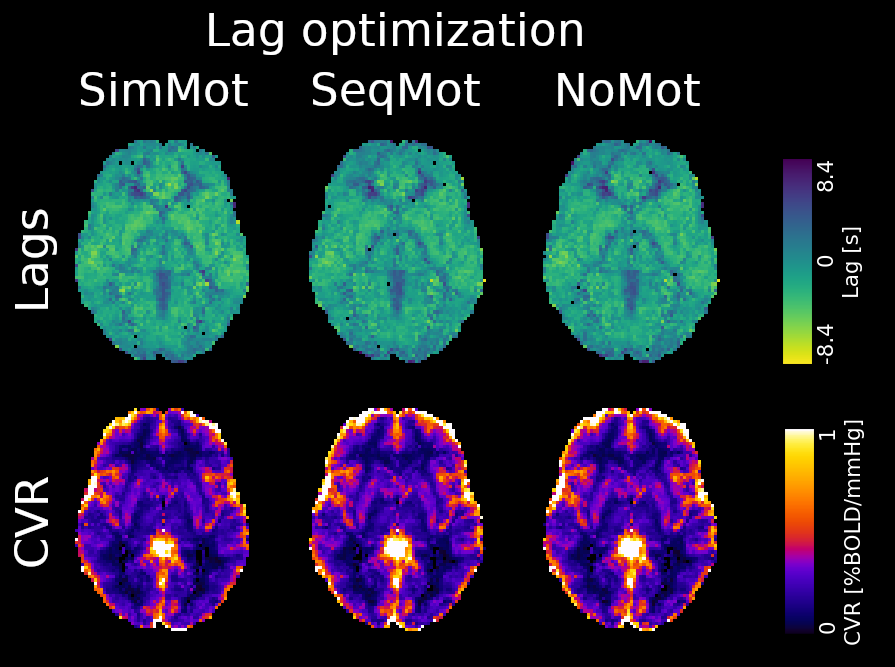

Methods: CVR and lag maps

CVR and lag maps: L-GLM with each lagged regressor and nuisance regressors (12 motion parameters and low frequency trends), voxelwise selection of the lagged model with highest explained variance (R²), normalisation to MNI152 template (2.5 mm isotropic)

We compared four pipelines:

- L-GLM with motion parameters (see above, SimMot): $$ Y = P_{ET}CO_2{hrf}_{vx} + Mot + Poly + n $$

- Non-optimised CVR map (measurement delay only, Non Opt): $$ Y = P_{ET}CO_2{hrf}_{bulk} +n $$

- L-GLM without motion parameters (NoMot): $$ Y = P_{ET}CO_2{hrf}_{vx} + n $$

- L-GLM without motion parameters, motion regressed out before (SeqMot): $$ [Y \perp (Mot,Poly)] = P_{ET}CO_2{hrf}_{vx} + n $$

Results: lag optimisation

| CNR of lag maps | SimMot | SeqMot | NoMot |

|---|---|---|---|

| GM-WM | 0.52 ±0.21 | 0.46 ±0.26 | 0.49 ±0.25 |

| GM-Putamen | 0.47 ±0.22 | 0.44 ±0.21 | 0.44 ±0.21 |

| GM-Cerebellum | 0.82 ±0.15 | 0.69 ±0.17* | 0.69 ±0.16* |

Non optimising leads to underestimate the CVR, especially in subcortical areas.

Lag maps show anatomical consistency

Different lag responses, coherent with previous evidence (e.g. Putamen has earlier response than GM)

Area mostly affected by motion! →

Moia, Stickland, et al. 2020 (EMBC)